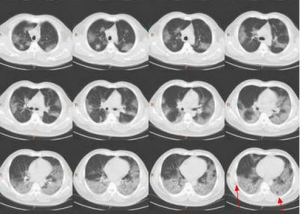

X線檢查往往在起病1周以後出現雙側間質瀰漫性格線狀、條索狀或斑點顆粒狀陰影,自肺門向外擴散,以後可融合成結節或雲霧狀,或有空洞形成。外周血白細胞計數與原發病有關,正常或稍高,嗜酸粒細胞計數增高。血氣分析有明顯的低氧血症,動脈血氧分壓常在60mmHg以下,動脈血CO2分壓正常或稍低,肺泡-動脈氧分壓差增大,可有呼吸性鹼中毒,晚期出現呼吸性酸中毒。肺總氣量、肺活量均減少,肺彌散功能減退。

其他輔助檢查:X線表現是非特異性的,10%~25%患者胸部X線可正常。典型的X線表現為瀰漫性肺間質浸潤,以網狀結節影為主,由肺門向外擴展。病情進展,迅速發展為肺泡實變,病變廣泛而呈向心性分布,與肺水腫相似。在實變病灶中雜有肺氣腫和小段不張,以肺的外圍最明顯。罕有氣胸或胸腔積液等胸膜病變。亦有以局限性結節陰影,單側浸潤為表現。肺功能檢查肺活量減低,肺彌散功能(DLCO)低於70%估計值。